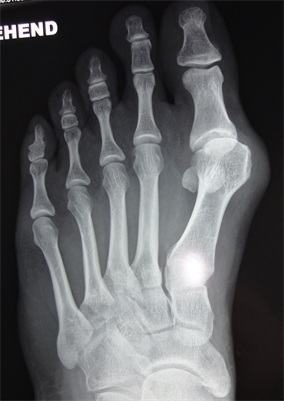

Figure 7. Patient Nr. 2. Hallux valgus with subluxed Ist MPJ and pathological DMAA.

Figure 8. Patient Nr. 2: Correction with 100% lateralization and only point contact of the osteotomy partners.

Figure 9. Patient Nr. 2. Result after 7 years. All components are corrected, no loss of lenght. Immediate full weight bearing, running after 8 weeks.

Figure 10. Patient Nr 2. Clinical appearance before the operation.

(a) (b)

Figure 11. (a) Patient Nr. 2. Result after 7 years; (b) Medic ballerina for undisturbed walking with bulky dressing or swellings